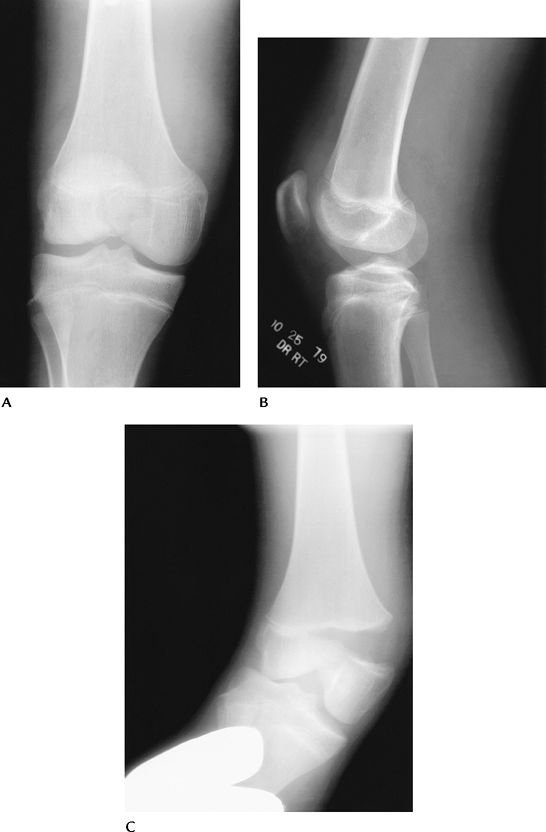

P.279

FIGURE 5-56 AP (A), lateral (B), and notch views (C) demonstrating characteristic appearance and location of osteochondritis dissecans (arrow). Note the lesion is most easily appreciated on the notch view.